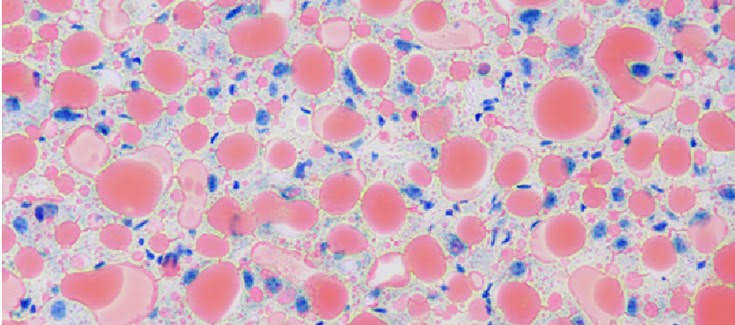

Desde 1980, el Dr. Ludwig había acuñado el término Esteato-Hepatitis, para designar el hallazgos de células hepáticas con grasa y con células inflamatorias alrededor. Poco a poco se le fue conociendo como Hígado Graso (en inglés Fatty Liver). En inglés esto suena como hígado gordo, gente gorda (fat people o fatty person) o gordita, lo cual puede ser peyorativo o discriminativo en la familia o en el trabajo.

Este hallazgo ocurría en personas que no consumían alcohol y poco a poco se le conoció como Esteato Hepatitis no Alcohólica (en inglés, NASH) y luego como Enfermedad por Hígado Graso no Alcohólico (en inglés se abrevia como NAFLD). Algunos médicos le decían a sus pacientes "usted tiene NASH" y trataban de convencerlos de que así era el nombre en inglés. Otros simplemente les decimos usted tiene Esteato Hepatitis, es decir una inflamación del hígado secundaria al exceso de grasa en su hígado.